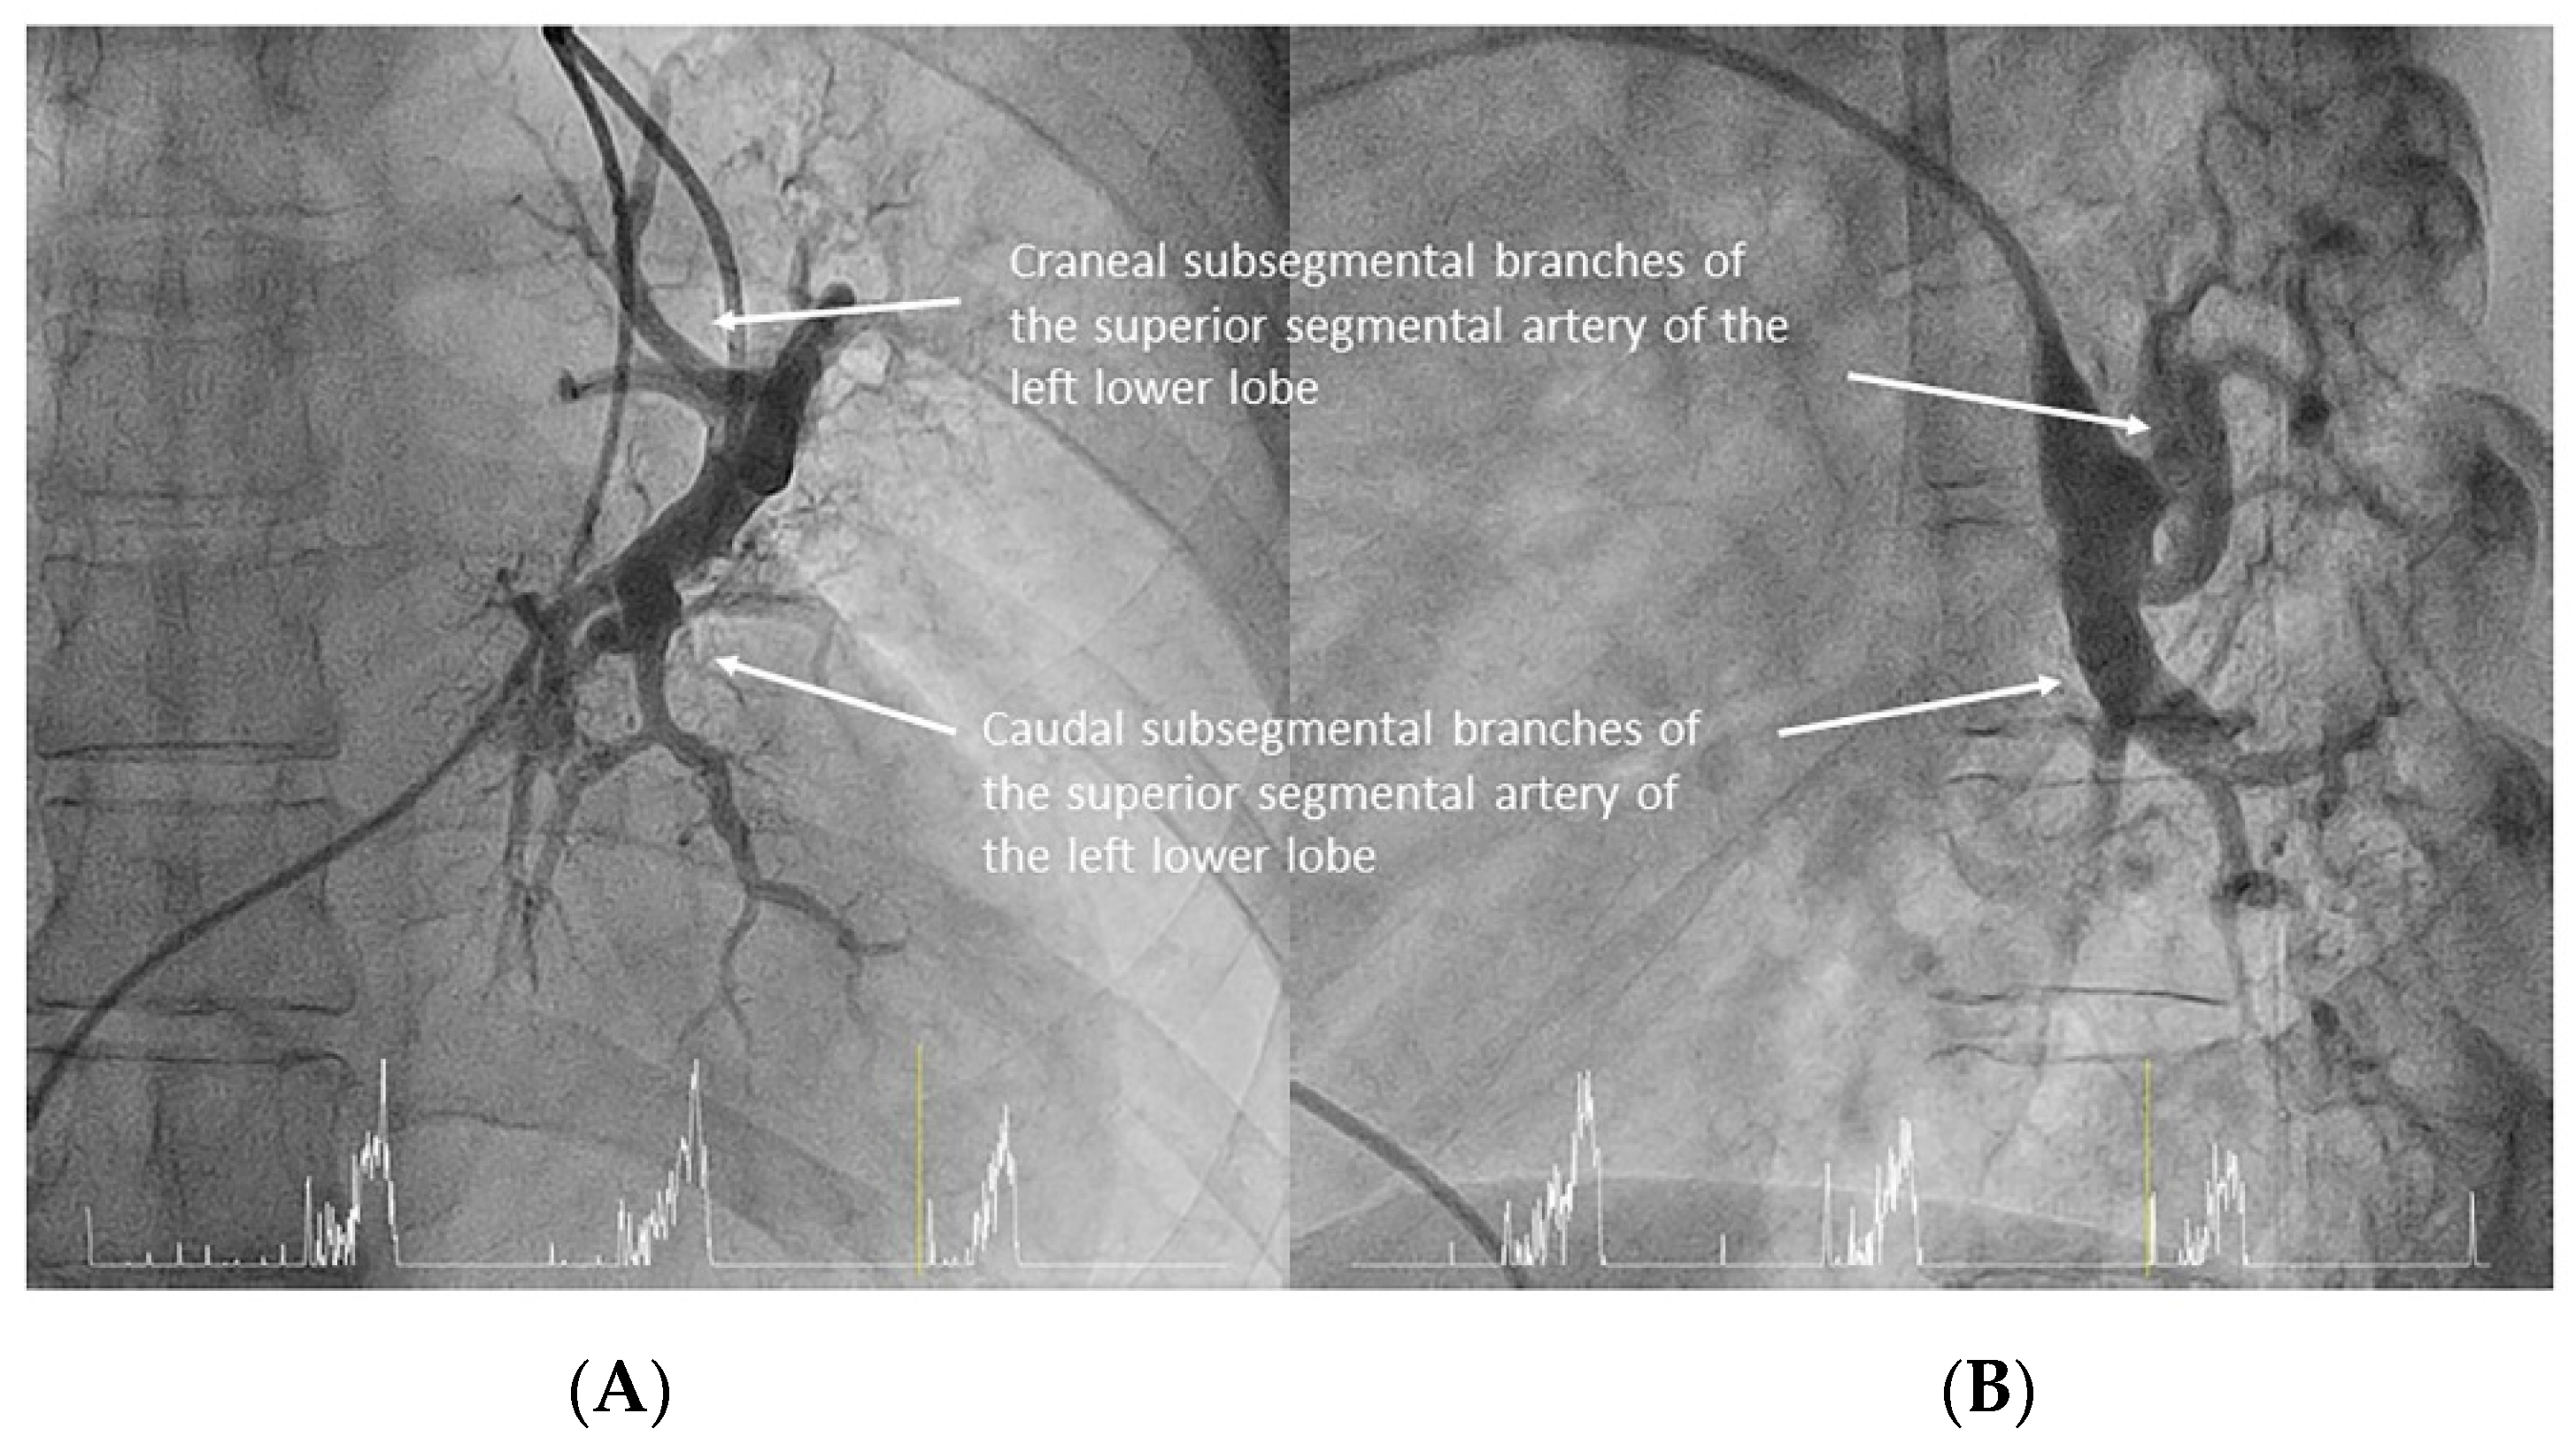

- Left lower lobe. The two trunks of the basal pyramid and the superior segmental artery (A6) are easily cannulated with the MP-A2 in the lateral projection (Figure 26). The anterolateral trunk (A8/9) sometimes requires the Judkins right (JR) 4 or the JL 3.5/4. We should sequentially film both trunks and the superior segmental artery (A6) in the lateral and AP view.

- Right lower lobe. The lateral projection and the MP are the best choices to canalize the two trunks of the basal pyramid and the superior segmental artery (A6). Use the AP and lateral views to assess the four segmental basal branches (Figure 32) and the lateral projection to display the superior segmental artery (A6) (Figure 16 and Figure 17).